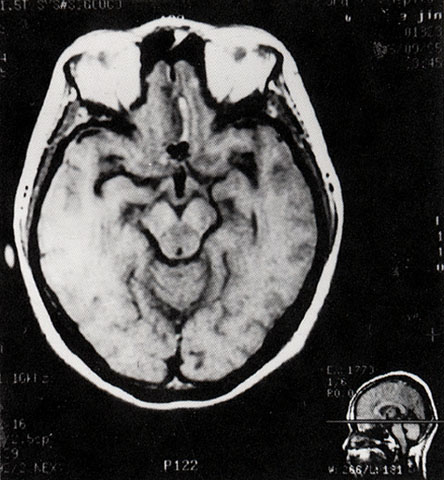

FH1040 脑动脉瘤(MRI)

光盘检索编码 FH1040  函授作业图编号 1040

图  名 脑动脉瘤(MRI)

导  学 与图1041、1042为同一患者